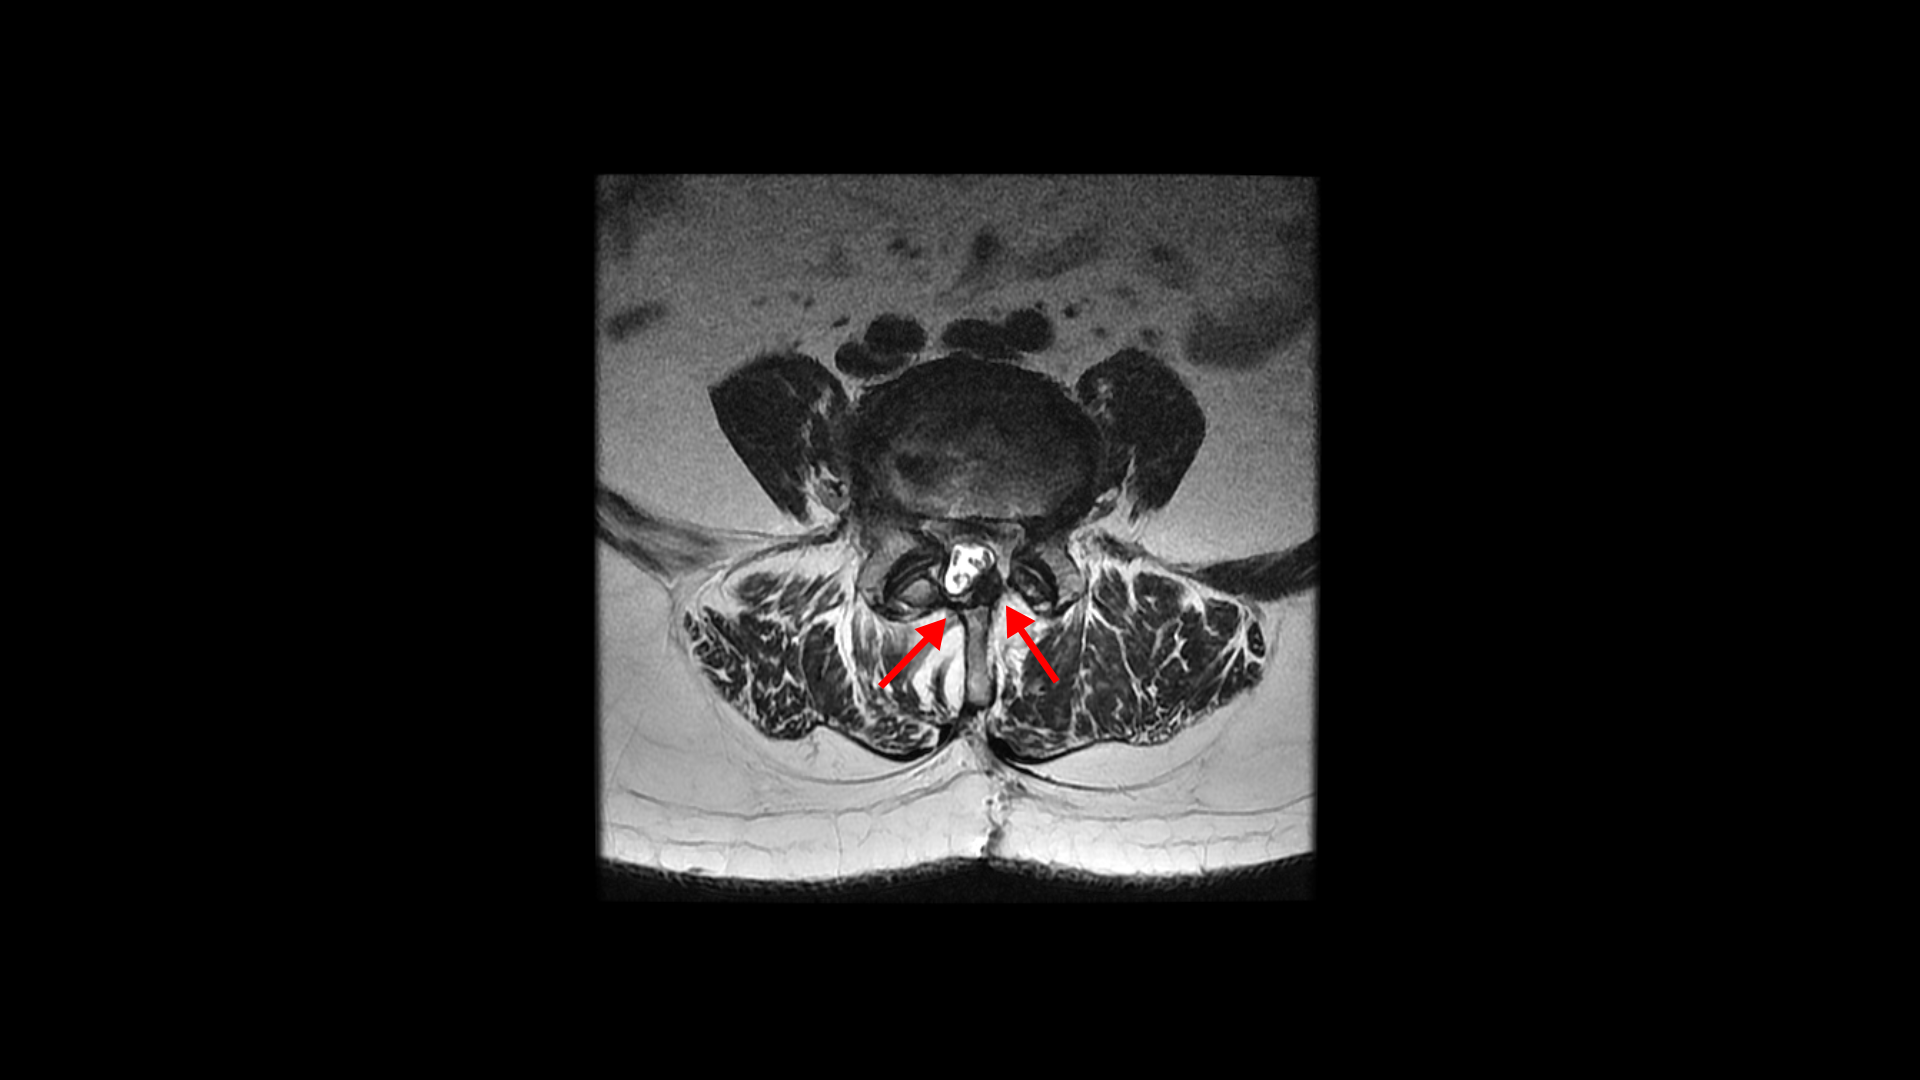

그런데 유합술 후 오른쪽 다리의 증상은 좋아졌으나 상대적으로 괜찮았던 왼쪽 다리에 심한 방사통과 마비 증상이 생겼습니다. 수술 후에 집도의로부터 수술은 잘 됐으나 수술한 자리가 부어있어서 신경을 눌러서 그럴 거니까. 1년 이상 기다리면 좋아질 것이라는 얘기를 들었습니다. 그런데 저희 모커리한방병원은 디스크나 협착증, 전방전위증 등으로 오랫동안 다리 방사통을 겪은 환자분들 중 수술받은 분들께 수술 후 남아있거나 새로 생기는 방사통이나 마비 증상은 회복을 위해 1년씩 혹은 그 이상 오래 기다릴 필요가 없다고 말씀 드리고 있습니다. 보통은 수술집도의 분들의 설명은 수술 전에 오래 눌려있던 신경이 다시 회복되는데 시간이 오래 걸리기 때문에 기다려야 한다고 얘기하는데, 저희 관점에서는 척추 수술 후 회복되는데 시간이 오래 걸리는 이유가 전혀 다릅니다.

저희가 보는 관점에서는 오랫동안 신경이 눌리고 방사통이 있던 분들은 허리 주변 근육은 물론 방사통이 있던 곳을 따라 엉덩이, 다리 근육들이 모두 심하게 뭉치고 굳고 망가지게 됩니다. 심한 분들은 근위축까지 와있는 분들도 많습니다. 또 더 심한 분들은 방사통 라인을 따라 고관절, 무릎 관절, 발목 관절의 가동성도 떨어지고 기능에 문제가 생깁니다. 이런 근육의 심각한 문제들과 관절의 문제들은 눌린 신경을 수술로 풀어준다고 해서 쉽게 자연적으로 빨리 회복되지 않습니다. 그래서 수술 후 통증과 마비 증상이 회복되는데 오랜 시간이 걸리는 겁니다. 그래서 이런 뭉치고 굳어버리고 망가진 근육을 직접 치료해서 굳고 뭉친 걸 풀어주고 기능을 회복시켜주면 수술 후 남아있는 통증과 마비 증상들이 훨씬 더 빨리 회복될 수 있는 것입니다.

실제로 수술을 잘해서 눌린 신경을 성공적으로 잘 풀어준 후에도 통증이나 마비가 남아있거나 안 아프던 다리에 통증이 새로 생기는 환자들이 많습니다. 그런데 다시 말씀 드리지만 수술 전 근육의 문제가 전혀 해결되지 않은 상태에서 수술을 하면 눌린 신경은 풀어주지만, 근육의 문제는 전혀 해결이 안 된 상태이고 또 수술 시 근육의 일부를 찢고 자르면서 근육에는 추가적인 손상을 주게 되니까 근육 문제는 오히려 더 심해질 수도 있습니다. 그래서 수술 후에도 다리 저림이나 마비 증상이 남아있거나 없던 증상이 새로 생길 수 있는 겁니다.

수술 병원에서는 수술로 눌린 신경을 잘 풀어주었으나 신경이 오래 눌려 있었기 때문에 신경이 회복되려면 길게는 1년 이상 기다려야 한다고 설명하지만 저희 생각은 완전히 다릅니다. 근육 상태가 상대적으로 좋았던 사람들은 금방 풀리는 사람도 있을 수 있지만 상태가 많이 안 좋았던 사람들일수록 빠른 시일 내에 자연적으로 쉽게 해결이 되지 않습니다. 이런 환자분들은 직접적으로 근육을 직접 치료해서 뭉치고 단축되고 굳어있는 문제들을 직접 해결해 주면 훨씬 더 빠른 회복이 가능합니다. 근육을 직접 치료하는 방법은 다양합니다. 침, 약침, 봉침, 부항, 추나요법, 도수치료, 재활 운동 등 다양한 방법으로 근육을 직접 치료합니다. 이 환자분도 역시나 수술로 신경 감압은 잘 되었지만 엉덩이와 다리 근육들이 극심하게 뭉쳐있는 상태였습니다.